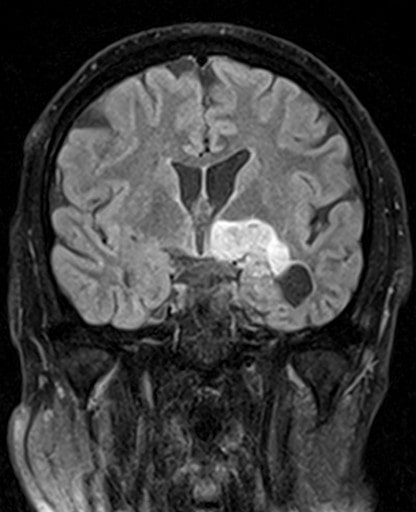

Cette masse peut entrainer notamment :

- Une irritation du cerveau qui se manifeste par une épilepsie

- Une compression voire destruction d’une partie du cerveau causant un affaiblissement ou une perte d’une fonction du cerveau

- Une augmentation de la pression à l’intérieur du crâne (espace inextensible à l’intérieur duquel vient s’ajouter le volume de la tumeur), ce qui va se manifester initialement par des maux de tête d’aggravation progressive qui vont s’associer à des nausées, des vomissements, des troubles visuels… Cet état peut aboutir à la perte de la vue dans les formes d’évolution lente et au décès dans les formes d’évolution rapide.